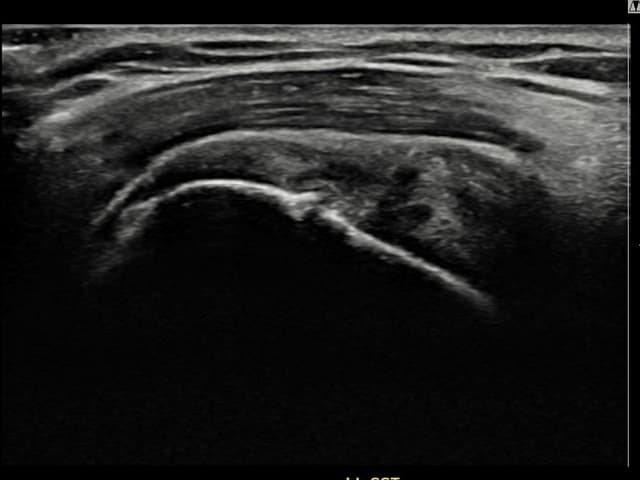

[촬영시기:22.09.19~22.12.09]

[어깨인대 축소봉합술] 우측 어깨 통증과 팔을 특정 각도로 올릴 때 심해지는 충돌 증상으로 내원하셨습니다.